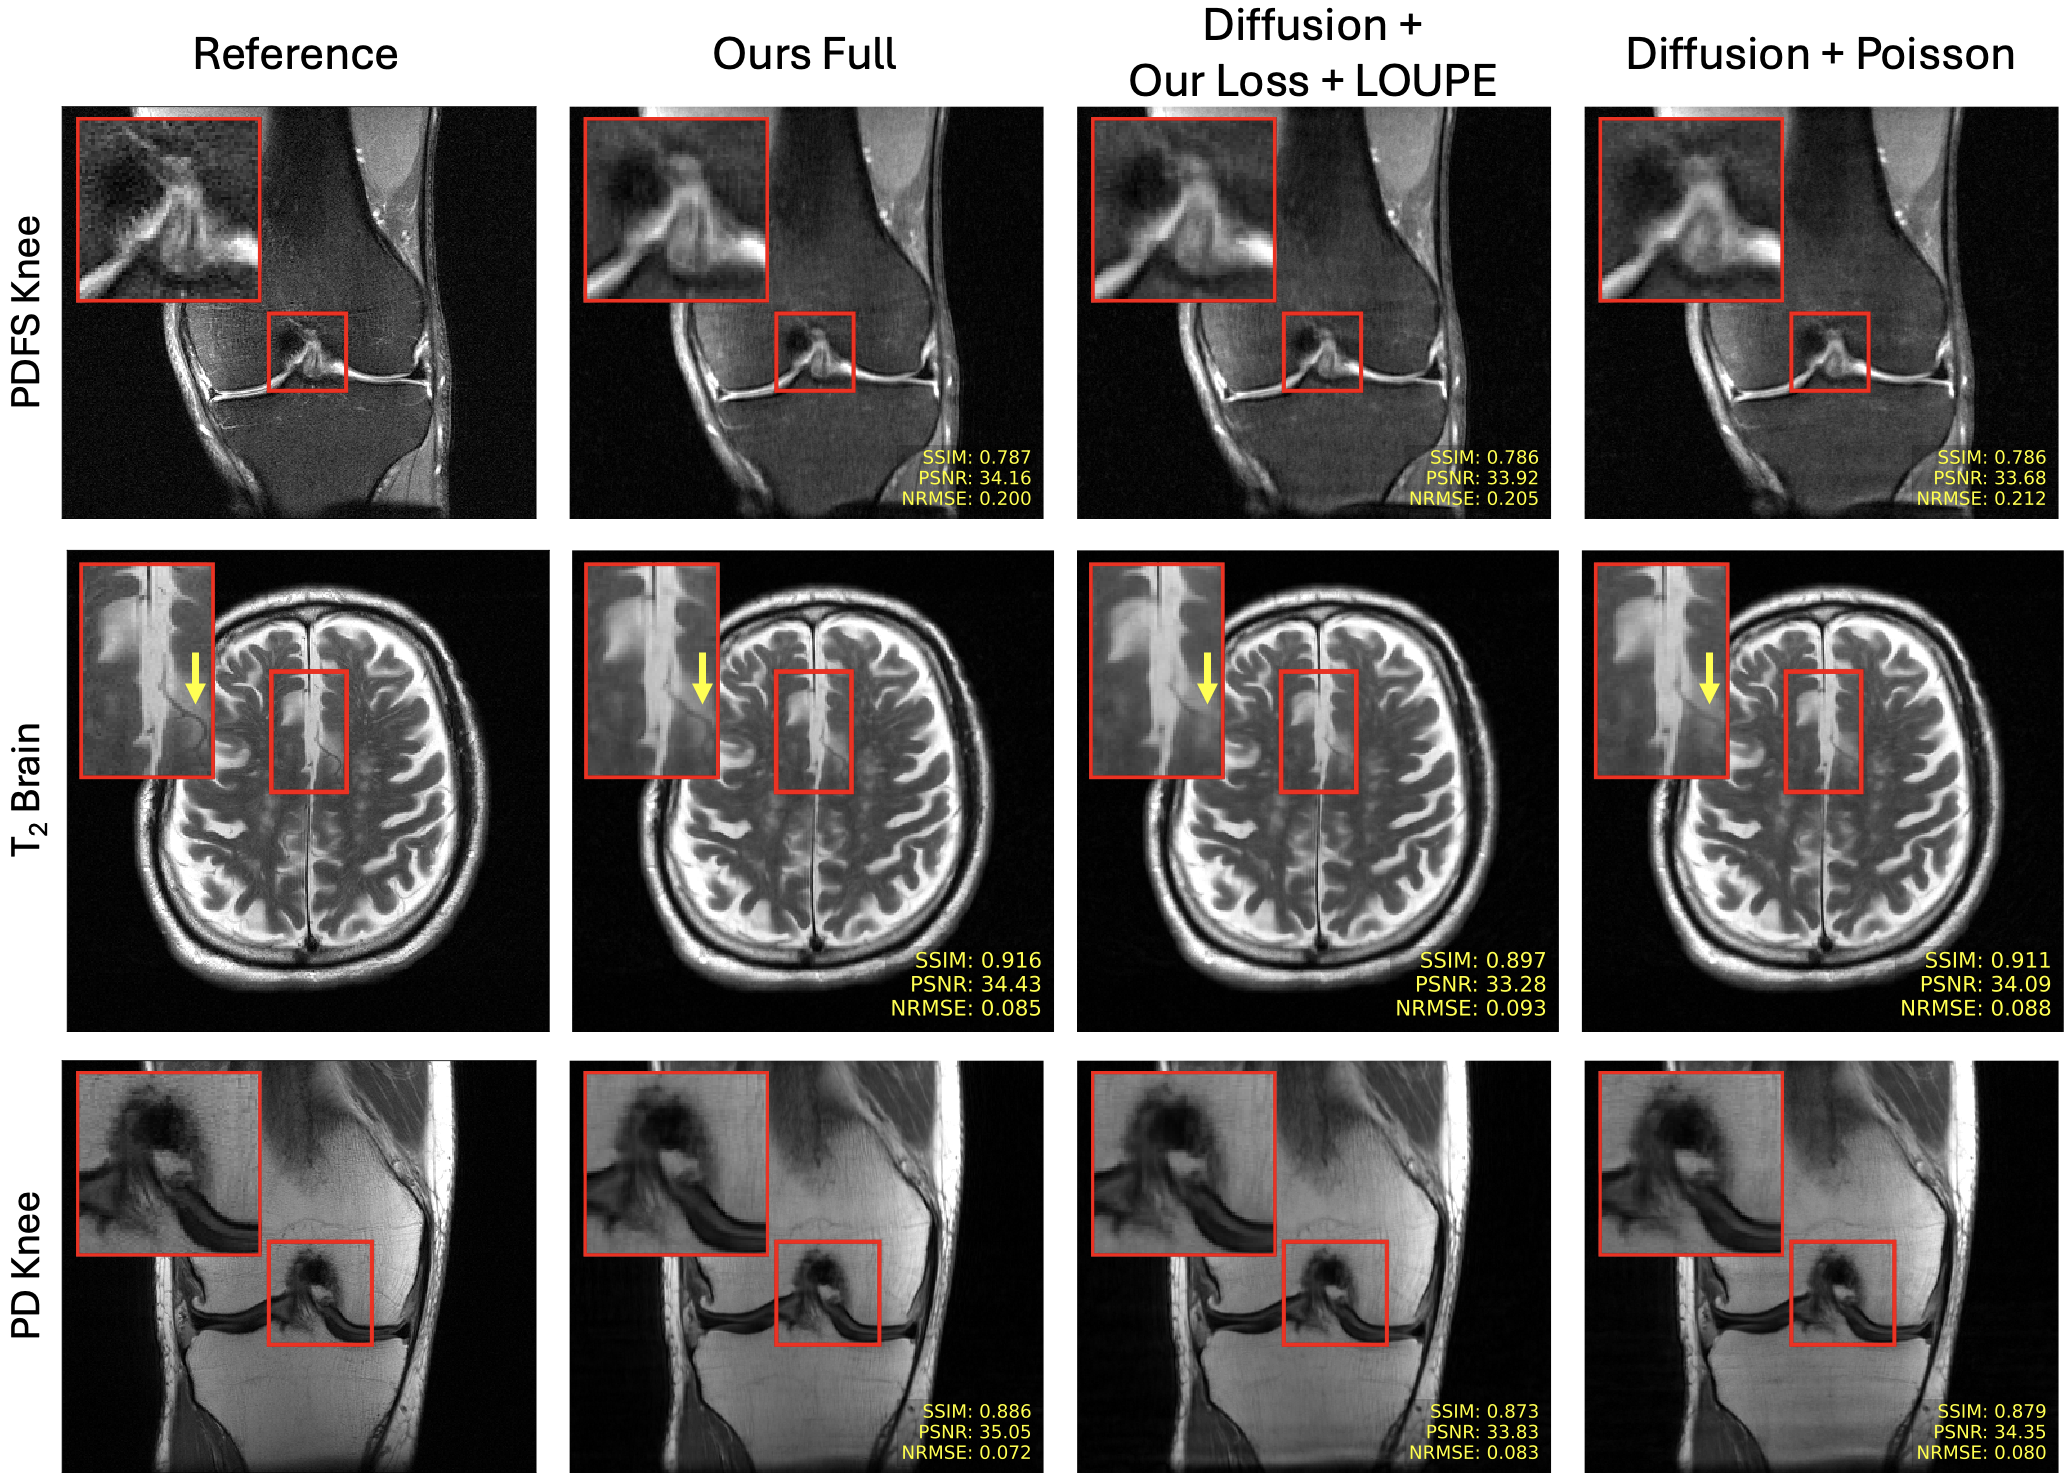

Fig. 3 presents slices reconstructed from k-space data under-sampled by with diffusion-models using a Poisson mask and masks optimized with our loss + LOUPE and our full method for PDFS knee, T2 brain, and PD knee data. Our full method achieves improved quantitative metrics, and the zoomed-in areas indicate that our proposed reconstruction produces slices with more fine structural details than those reconstructed with the other diffusion model-based methods. Similarly Fig. 4 and Fig. 5 show reconstructed slices, along with error maps, at and for T2 brain and PD knee data respectively. Again, our method, with its optimized sampling pattern, achieves improved quantitative and qualitative performance in comparison to the competing diffusion-based methods.

Fig. 6 presents quantitative comparisons of peak signal-to-noise ratio (PSNR), structural similarity index measure (SSIM) [50] and normalized-root-mean-square-error (NRMSE) of reconstructed slices with acceleration factors of . Our full method outperforms the other two diffusion-based methods across all anatomies, metrics, and accelerations, suggesting that our approach for learning sampling patterns may be better suited for diffusion-based reconstructions in comparison to Poisson Disc patterns and multi-coil LOUPE. Quantative MoDL results are also presented for reference. Since MoDL optimizes an NRMSE objective end-to-end during training, it generally achieves similar or lower NRMSE and PSNR in comparison to the diffusion-based methods. However, the proposed diffusion-based method achieves better SSIM than the end-to-end methods in all settings but PD knee data, where the two methods perform comparably.